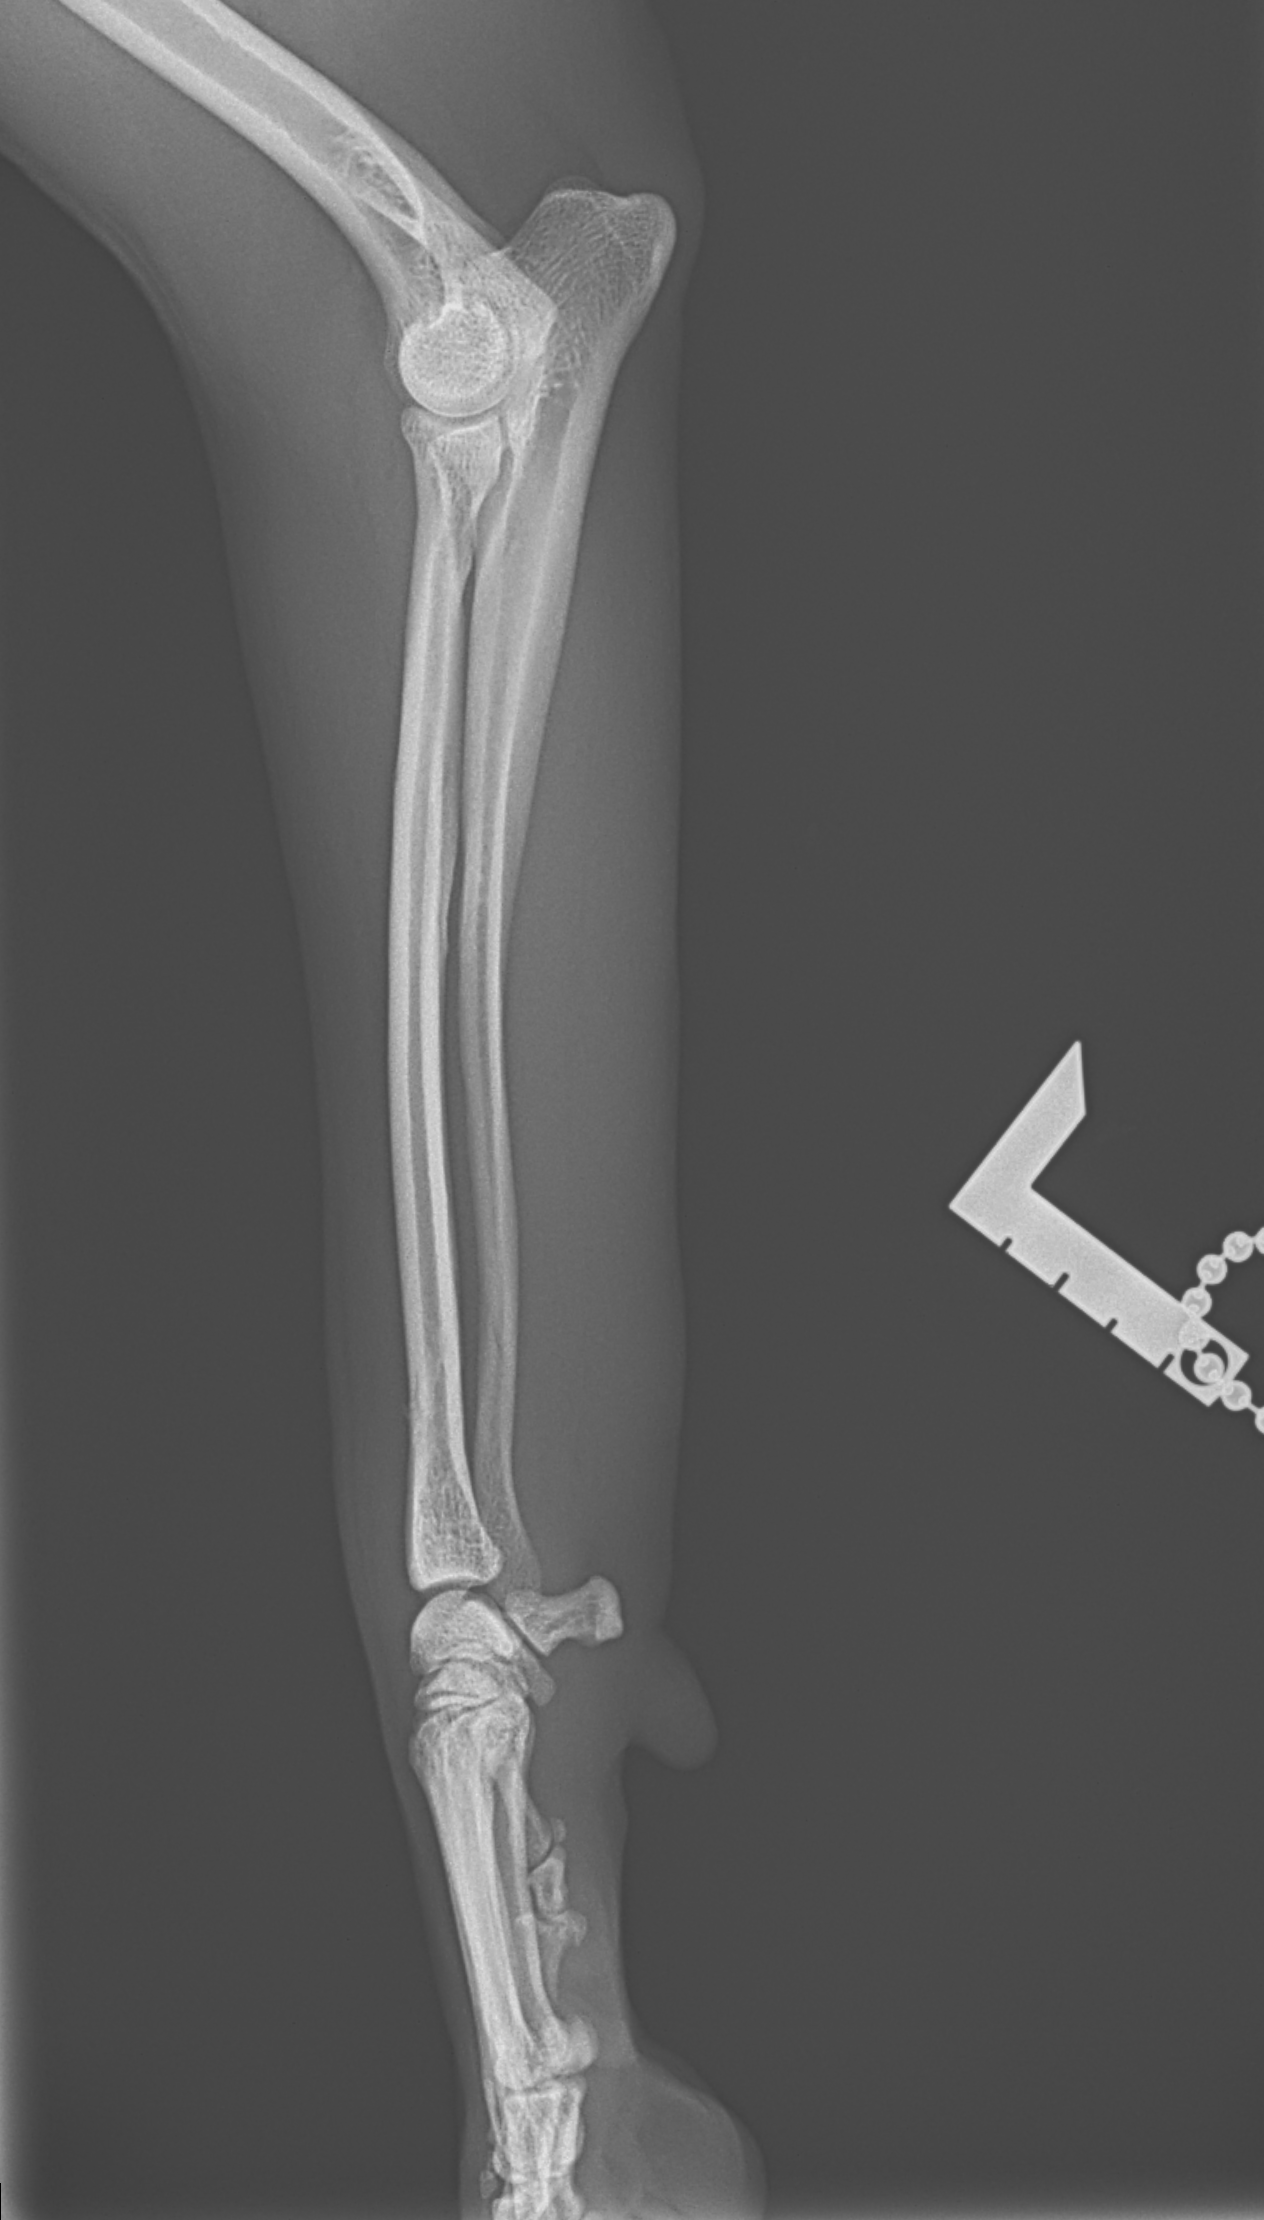

橈骨固定術 #266 6歳のワンコが落下事故により橈骨骨折をしたとの事。関節近傍から斜骨折をしています。1.5のPosition Screw、2.0 TH Plateで固定術を行いました。しばらくは安静が必要です。 症例カテゴリー 放射線治療整形外科軟部組織外科脳神経外科内科腫瘍外科救急・集中治療リハビリテーション科腫瘍内科内視鏡科脳神経科呼吸器外科中医・漢方猫の腎移植循環器科